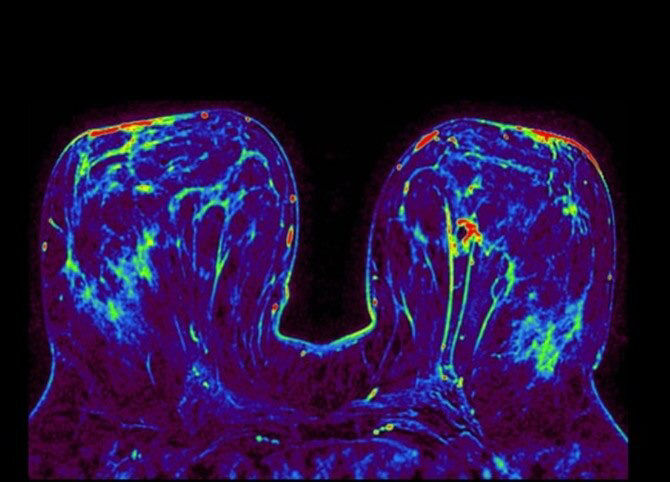

Our boldest ideas yet

Meet our next-generation SIGNA MRI scanners & solutions

SIGNA MRI Scanners

Our 1.5T, 3T, PET/MR and 7T scanners deliver the latest in imaging innovation with AIR Recon DL, and AIR Coils.